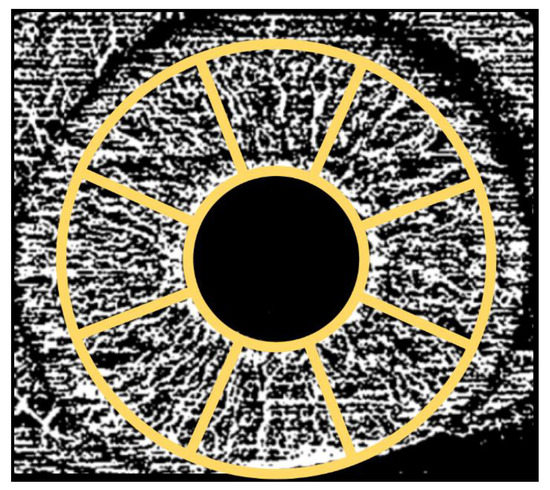

2.3. Imaging

2.4. Image Processing